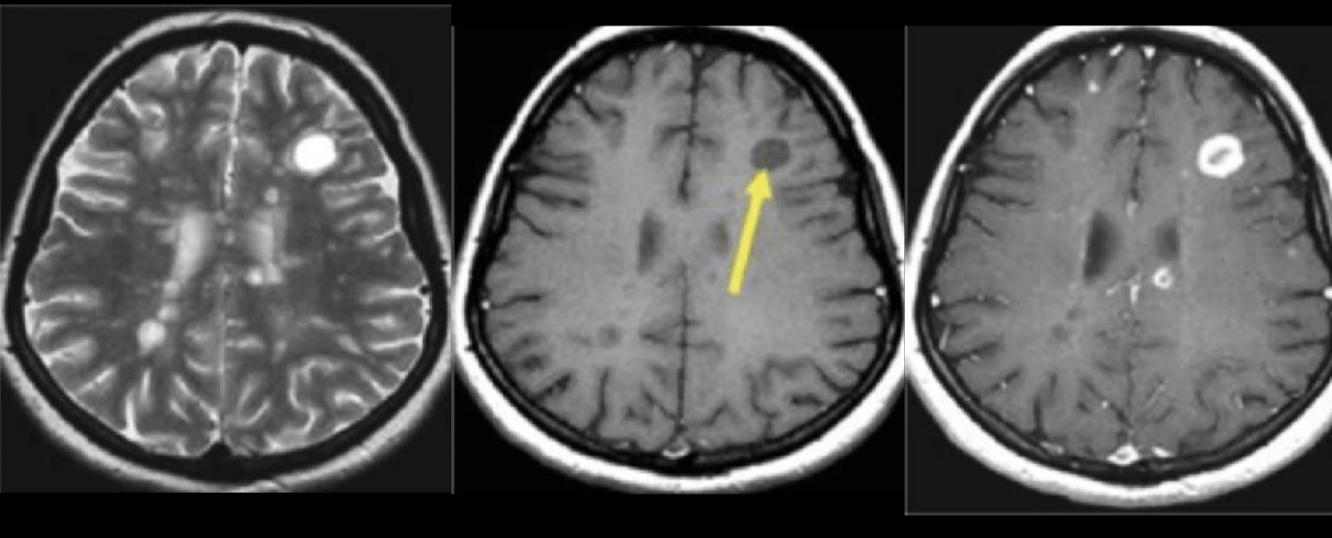

RM que vemos

Hiperintensidades calloseptales en T2 y flair

Pequeñas 5-10 mm, lineales y ovoides

Dedos de Dawson periventriculares

Como se ven las lesiones en T1

Hipointensas: black holes: crónicas

T1 + GD

Captación: agudas: activas